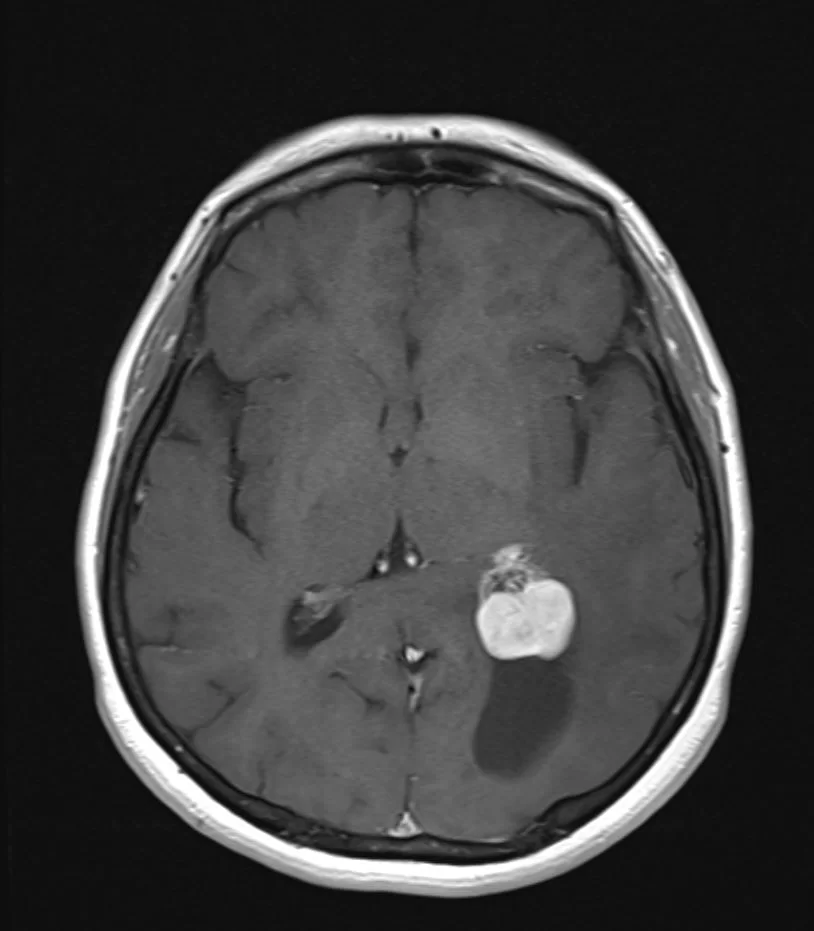

Ενδοκοιλιακό Μηνιγγίωμα

Ασθενής άνδρας, 49 ετών με επίμονες κεφαλαλγίες και τον τελευταίο καιρό και διαταραχές όρασης αριστερά. Η μαγνητική τομογραφία ανέδειξε χωροκατακτητική

Ενδοκοιλιακό Μηνιγγίωμα Δεξιά

Ασθενής γυναίκα, 59 ετών παρουσίασε επεισόδιο επιληπτικής κρίσης. Η μαγνητική τομογραφία ανέδειξε ευμεγέθη χωροκατακτητική εξεργασία εντός της δεξιάς πλάγιας κοιλίας

Ευμεγέθες Ενδοκοιλιακό Μηνιγγίωμα Δεξιά

Ασθενής γυναίκα, 70 ετών παρουσίασε επιληπτικές κρίσεις και αριστερή ημιανοψία. Η μαγνητική τομογραφία ανέδειξε ευμεγέθη χωροκατακτητική εξεργασία εντός της δεξιάς